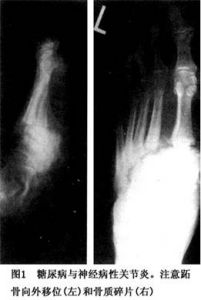

梅毒的脊髓亞急性聯合變性、截癱Charcot-Marie-Tooth病、軟弱,痛覺減低和位置覺障礙等,可使膝關節(其次是髖、踝、脊柱等處)大為破壞是為此病的典型表現。脊髓空洞症時最常累及的是肩和上肢。提示膝/踝神經病性關節病的證候是:關節積液、摩擦音和關節增大而疼痛相對輕微(但至後期疼痛亦可加劇)。糖尿病性關節病(圖1)時的神經病性關節病,是使病程久遠和有感覺神經病的患者,一或兩足發生無痛性腫脹。由於機械性原因,最常受累的是跗跖和跖趾關節。距骨、跟骨、踝關節和脛骨遠端也能發生破壞。放射線像上的特徵是關節腔消失、硬化、反映碎片骨折的多發性不規則小體以及新骨形成等,骨髓炎時也能見到類似改變。二者鑑別可能很難,磁共振成像(MRI)可能有助。(焦磷酸鈣沉積病時也有與此相似而程度較輕的改變報告。)據認為,糖尿病時的早期改變是破骨細胞作用亢進引起的治療急性關節病,須立即減輕載重。試圖以各種矯形器材以使受累關節獲得穩定的作法,收效多不滿意,手術融合亦甚困難全膝/髖成形術可能有益。

1.X線檢查 早期X線表現為關節的退行性改變,關節面輕度硬化侵蝕及破壞。病變晚期受累骨的關節端硬化更明顯,伴骨質增生、破壞骨膜反應,關節畸形。關節面不規則、塌陷,關節間隙變窄關節脫位或半脫位關節周圍軟組織腫脹,軟組織內可見不規則鈣化斑或碎骨片。